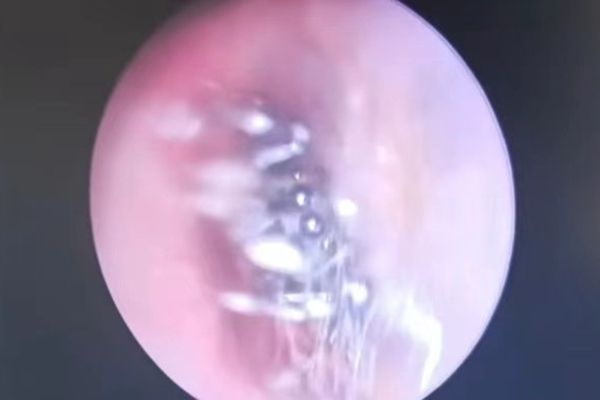

女子耳鸣听力下降 竟是蜘蛛在耳道结网

中国四川省凉山彝族自治州会东县一名40岁女子近日因为左耳出现耳鸣、听力下降等症状,而前往医院耳鼻喉科挂号就诊,没想到医生检查后,发现女子耳朵里长满蜘蛛丝,竟是有蜘蛛在耳朵内“定居”,最终成功将蜘蛛取出,女子的耳道也没有大碍。

综合陆媒报道,耳鼻喉科医生韩兴龙透过耳内镜检查时,发现女子的耳道满布白色的丝状物,初时以为是霉菌性外耳道炎,他再仔细查看时,越看越不对劲,便着手清除丝状物,耳道里突然钻出一只生物,原来竟是一只蜘蛛。

蜘蛛在女子的耳道内逃窜,韩兴龙花了一番功夫才顺利将它夹住、取出,幸好这只蜘蛛没有毒性,因此女子除了耳道有些损伤以外,其余并无大碍。